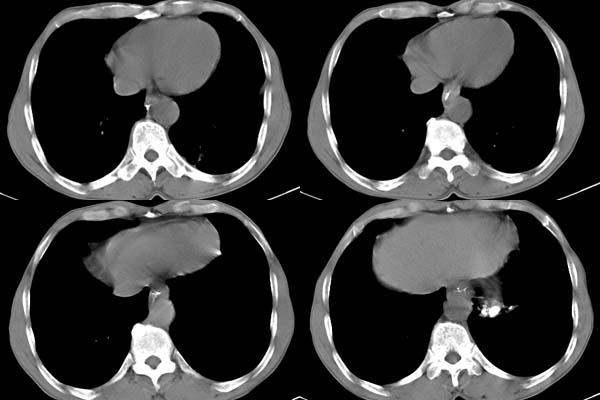

ct所见;左下肺可见片状阴影,密度不均,边缘尚清晰,胸膜方向见有条索相连,纵隔窗未见具体结节。左侧胸膜下见多个软组织结节且以宽基底与胸膜相连,右侧胸锁关节层面亦见软组织结节广基与胸膜相连。纵隔未见肿大淋巴结,气管,支气管开口正常。

2,胸膜病变,以胸膜间皮瘤可能性大。

胸膜病变,以胸膜间皮瘤可能性大

考虑:周围型肺ca伴左侧胸膜转移可能性大 ,不完全除外左肺下叶炎性假瘤,左侧胸膜间皮瘤可能,建议强化ct扫描。

支持:周围型肺ca并多发胸膜转移.胸膜间皮瘤不能除外.建议强化

支持胸膜间皮瘤